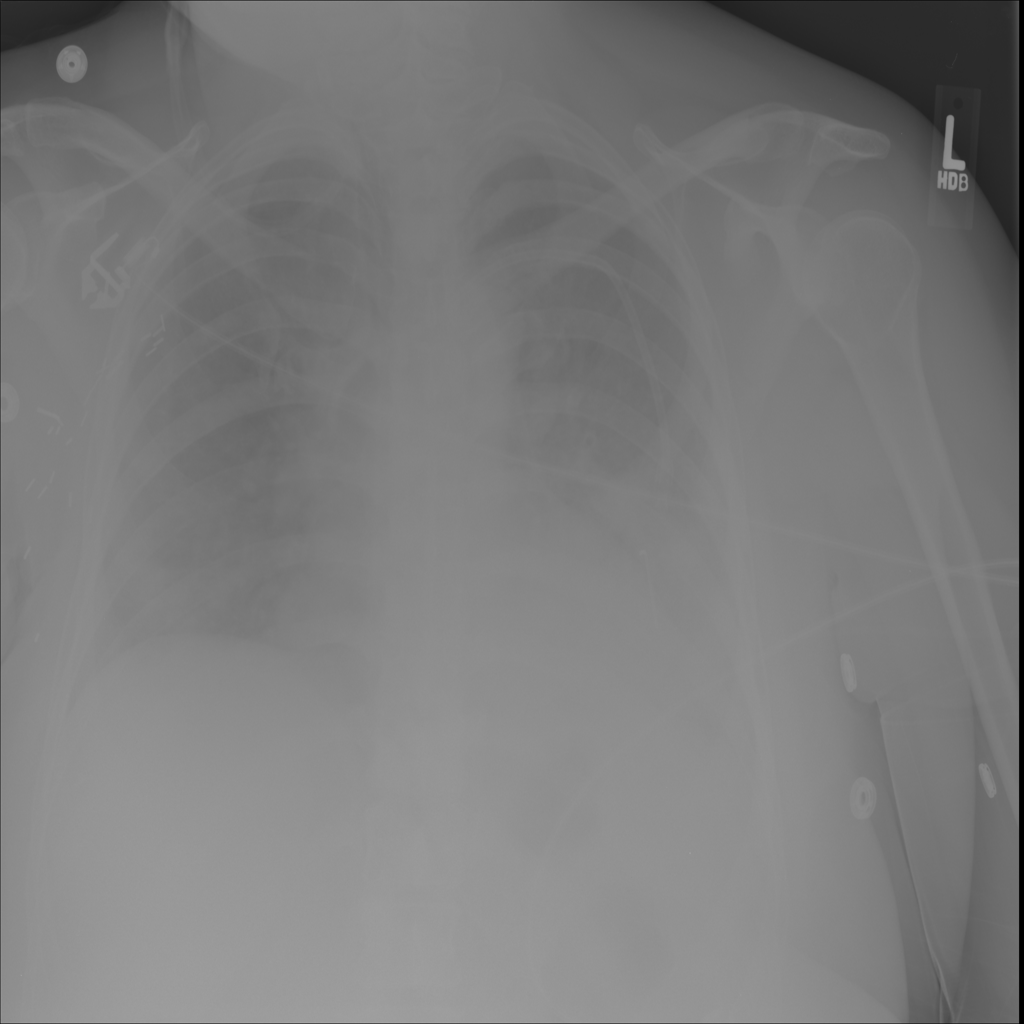

Mass

A mass is a larger focal opacity or lesion seen on the image. It is a descriptive finding that can have several causes and usually needs more imaging or clinical context to characterize.

PAT-C0E5 · IMG-001Mass

PAT-C0E5 · IMG-001

PA